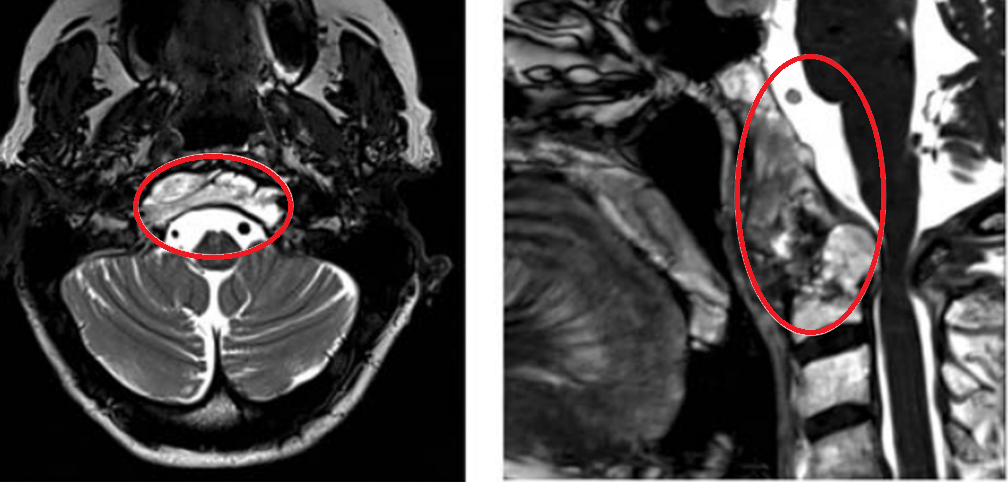

术前MRI

26岁男性患者因巨大颅颈交界区脊索瘤(96.5cm³)导致严重神经压迫症状,福教授采用双镜联合“筷子技术”经远外侧入路全切肿瘤,脑干得到解压,并运用改良Roy-Camille枕颈融合术为质子治疗预留通道,术后患者神经功能明显改善并顺利完成后续治疗。